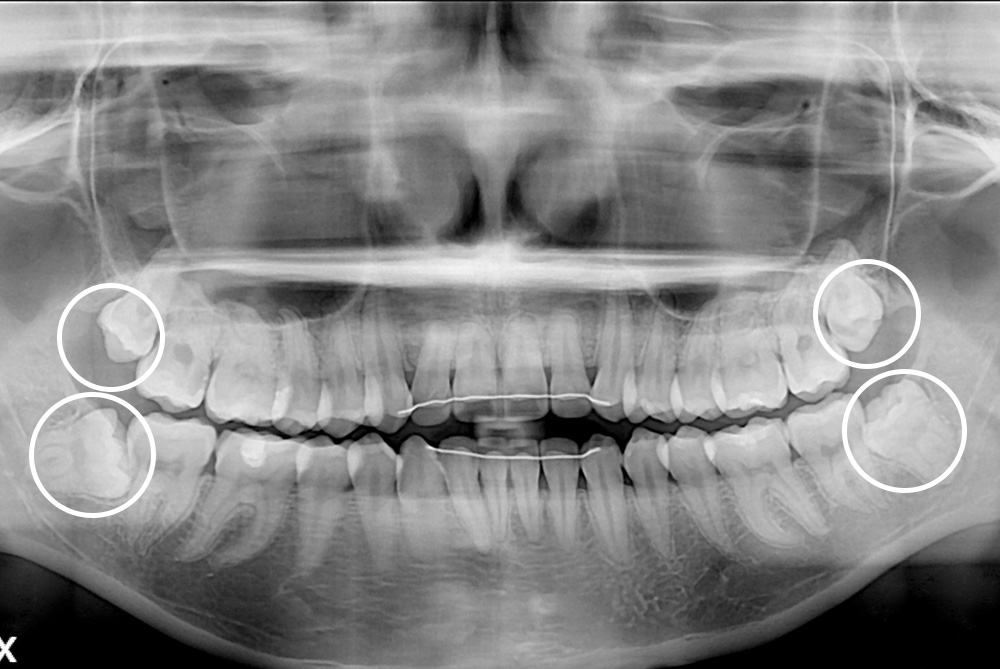

[사랑니] 매복 사랑니 발치

치료후 : 2021-05-15

세종치과는 구강악안면외과학 박사이신 원장님이 발치하는 치과입니다.